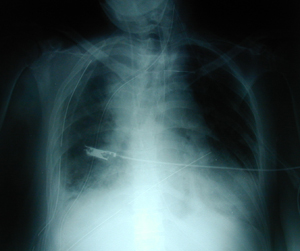

Εικόνα 1

Οπισθιοπροσθία ακτινογραφία θώρακος ασθενούς που είχε εργώδη διασωλήνωση για χολοκυστεκτομή. Υπάρχει μεγάλη υπεζωκοτική συλλογή στο δεξιό ημιθωράκιο, υπάρχει υδραερικό επίπεδο στο ημιθωράκιο όπως και αέρας στο μεσοθωράκιο και στον τράχηλο.